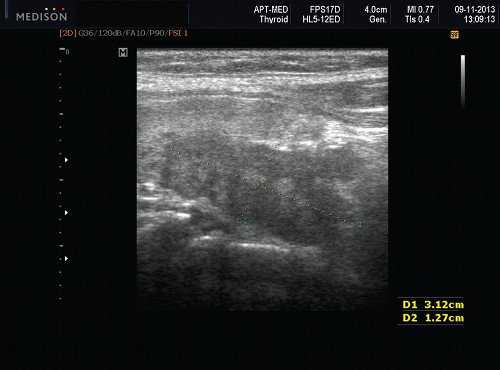

Плеоморфная (полиморфная) аденома (смешанная опухоль СЖ) - аденома СЖ, построенная из двух типов клеток: эпителия протоков и миоэпителиоцитов. Макроморфологическая картина. Опухоль обычно представляет собой эластичный или плотный узел дольчатой серовато-белой ткани, как правило, инкапсулированный частично. Типичной для плеоморфной аденомы является так называемая хондроидная строма, напоминающая гиалиновый хрящ. Варианты эхографического изображения плеоморфных аденом представлены на рисунке 8.